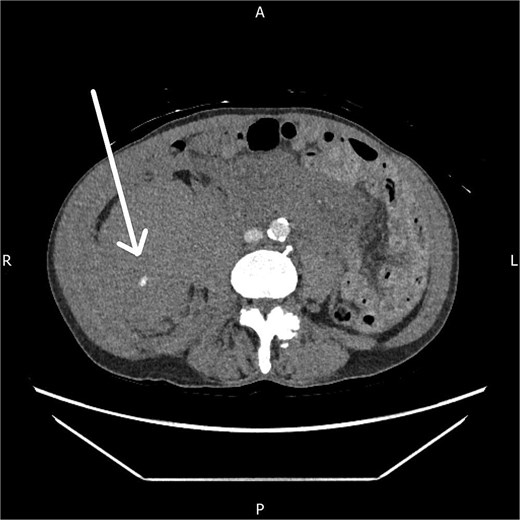

The CT angiogram, performed 14 hours after presentation, showed a further increase in the size of the haematoma with ongoing active arterial contrast extravasation (Fig. 2). Despite the clear need for embolization, the interventional radiology team was unavailable due to a concurrent emergency life-saving procedure.

Axial CT angiogram showing persistent right-sided retroperitoneal haematoma with ongoing active contrast extravasation.